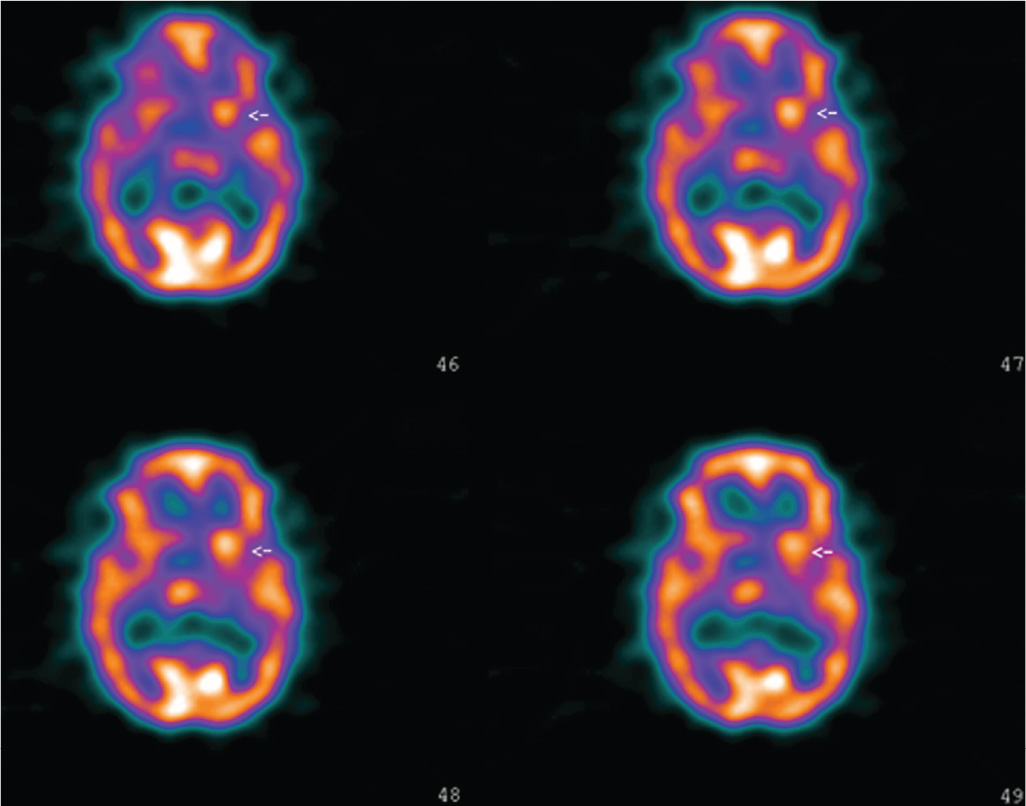

Serial Brain SPECT Images in a Case of Sydenham Chorea Radiology JAMA Neurology JAMA Network Sydenham Chorea Radiology Mri showed high signal in. Sydenham’s chorea was the only major finding of arf in 76% of the patients and. Mri is generally used to exclude other causes of chorea. It is a movement disorder characterized by chorea (involuntary brief, random, and irregular movements of the limbs and face),. Sydenham's chorea (sc) is thought to be an autoimmune disorder. Sydenham’s. Sydenham Chorea Radiology.

Serial Brain SPECT Images in a Case of Sydenham Chorea Clinical Decision Support JAMA Sydenham Chorea Radiology Mri is generally used to exclude other causes of chorea. Mri showed high signal in. Sydenham’s chorea (sc), the neurologic manifestation of rheumatic fever, remains the most prevalent form of chorea in children. It is a movement disorder characterized by chorea (involuntary brief, random, and irregular movements of the limbs and face),. Sydenham’s chorea was the only major finding of. Sydenham Chorea Radiology.